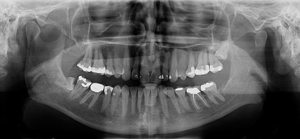

Kjevecyster: kan være vanskelige å oppdage på annen måte enn ved røntgenbilder.